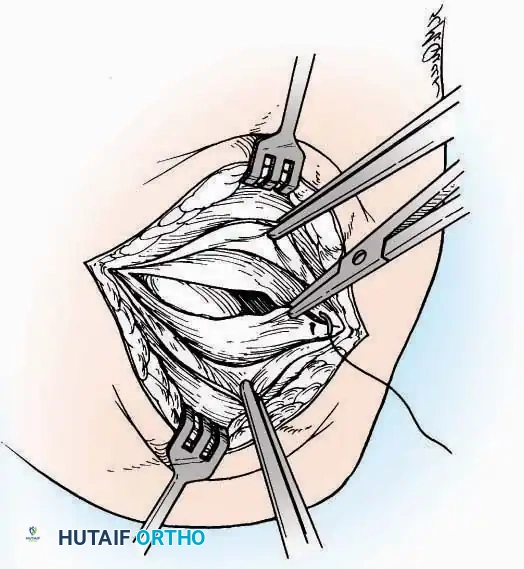

Surgical Technique:

* Incision: Begin the incision on the lateral margin of the Achilles tendon near its insertion. Extend it distally to a point 4 cm inferior and 2.5 cm anterior to the lateral malleolus. (For trauma, a classic L-shaped extensile incision is often used, dropping straight down anterior to the Achilles, then curving gently toward the base of the 5th metatarsal).

* Superficial Dissection: Divide the superficial and deep fasciae. It is imperative to create a "full-thickness" flap containing skin, subcutaneous fat, and periosteum to prevent flap necrosis.

* Nerve Protection: The sural nerve crosses the proximal and distal limbs of this approach. It must be identified and protected within the anterior flap.

* Deep Dissection: Isolate the peroneal tendons (longus and brevis). Incise and elevate the periosteum below the tendons to expose the lateral wall of the calcaneus.

* Tendon Management: If severe deformity or infection is present, the peroneal tendons may be divided via Z-plasty and repaired at the conclusion of the case, though this is rarely necessary in modern fracture care.